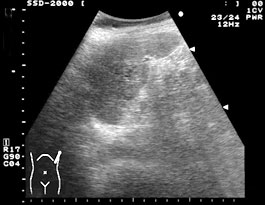

![]() 左側背部打撲による脾臓の鈍的外傷(挫傷)の症例. |

![]() 保存的治療による1週間後の超音波像である. |